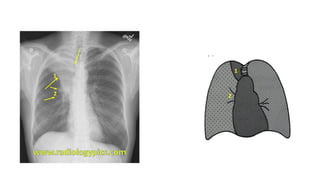

The document presents a chest X-ray examination summary by Ninian Peckitt, detailing various respiratory conditions including tracheal deviation, pleural effusions, and lung collapses. Findings suggest thoracic trauma and hyperinflation in the lungs. Additionally, it includes links to medical products and their pricing.